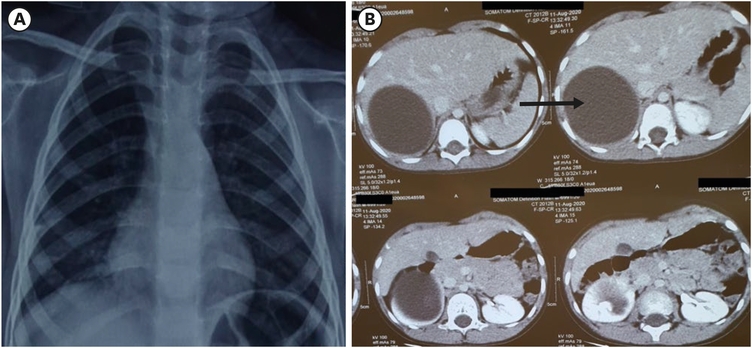

A 6-year-old male child (126 cm height, 26 kg weight, body mass index of 16.88 kg/m2) resident of Himachal Pradesh, India, presented with vague abdominal pain for the past 2 years. There was no history of abdomen distension, hematuria, dyspnea, chest pain, loss of weight, or contact with a pet animal or TB patient. There was no similar history among the family members. The child was hemodynamically stable and on examination, a firm lump was palpable in the right lumbar region. Ultrasonography (USG) showed a cystic mass (7.3×7.2 cm) with internal echoes at the right suprarenal location. Chest X-ray was normal and there were no specific changes (Fig. 1A) The contrast-enhanced computed tomography (CECT) abdomen (Fig. 1B) showed an 8.7×6.6 cm cystic lesion arising from the upper pole of the right kidney, with fine internal septations. No enhancing solid component, fat, calcifications, or air was seen in the lesion. The lesion has a large exophytic component which was scalloping the posteroinferior surface of the right lobe of the liver. The renal vessels were normal. The blood investigations including complete blood count (haemoglobin 11.7 g/dL, white cell count 13,700 cells per mm3, platelets 373,000 per mm3, eosinophils 4%), renal function test (urea 23 mg/dL, creatinine 0.7 mg/dl), and liver function test (total bilirubin 0.39 mg/dL) were normal, serological test (indirect hemagglutination) for HD was negative. On clinical presentation and radiological images, the possibility of a cystic variant of Wilms tumor (WT) was kept and the child was taken up for exploration with the consent of right partial nephrectomy. On laparotomy, a tense cystic lesion was noted arising from the upper pole of the kidney (Fig. 2A), abutting the lower surface of the liver. On aspiration, 70 mL of clear fluid (hydatid fluid) was aspirated from the cyst, 10% betadine was instilled into the cyst and kept for 20 minutes, re-aspiration was done followed by deroofing of the cyst (Fig. 2B), a single hydatid cyst (size 10×8 cm) was removed without any spillage. A drain was placed in the cyst and the abdomen was closed. The post-operative period was uneventful. The histopathology report (Fig. 2C) of hydatid fluid and excised cyst wall turned out to be hydatid cyst with tuberculosis i.e., presence of AFB bacilli along with hydatid. The pediatric pulmonologist’s opinion was taken, and the child was started on anti-tubercular treatment (ATT). In ATT regimen, child had received isoniazid (H), rifampicin (R), ethambutol, and pyrazinamide for 2 months followed by 4 months of H and R. At the same time, child had also received 3 cycles of albendazole and each cycle comprise of albendazole 10 mg/kg/day for 21 days followed by 3 weeks gap before next cycle. At 6-months follow-up, the child was doing well and on USG abdomen there was no residual cavity.

Fig. 1

Showing X-ray chest (A) with no specific changes and computed tomography scan abdomen (B) showing large cystic lesion at the upper pole of the right kidney.